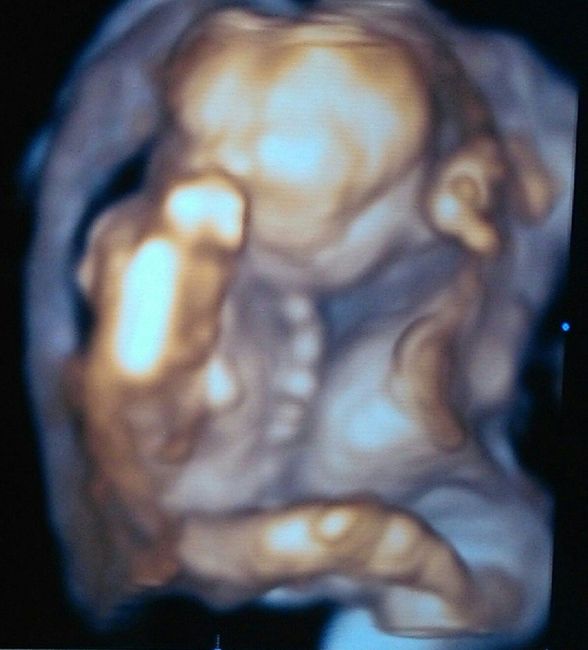

Buongiorno mammine e future mammine.... all'ultimo controllo,dove abbiamo scoperto anke ke avremo un bel maschietto,il nostro ginecologo ci ha fatto l'ecografia in 3D.... è stupendo. Vederlo e sentirlo e ogni volta una grande emozione....nn vedo...